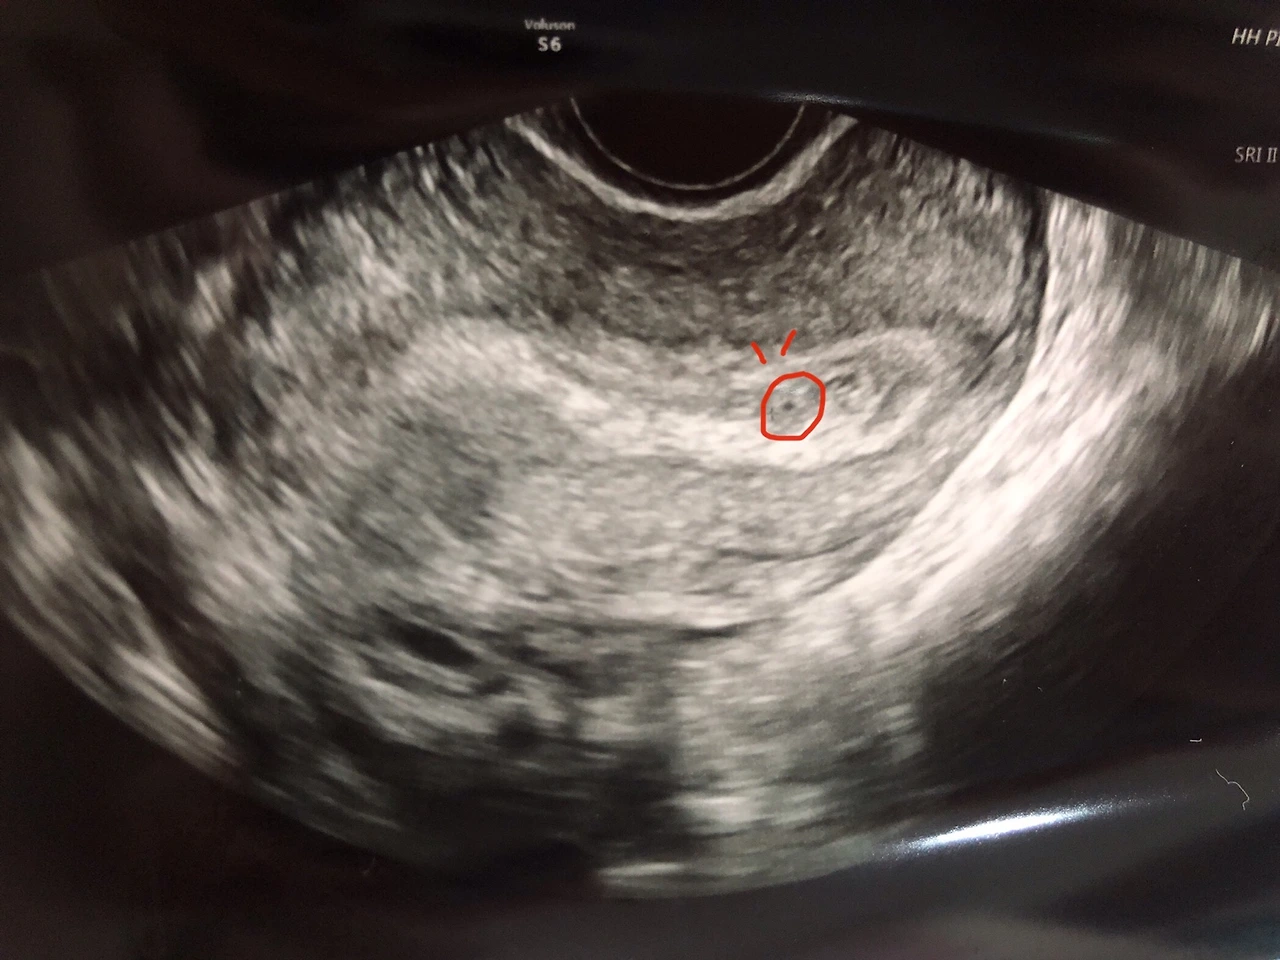

축하해 주세요! 여러분! 새로운 식구가 생겼습니다. 아들인지 딸인지 말랐는지 뚱뚱한지 키가큰기 작은지 똑똑한지 재주꾼인지 알 수는 없지만! 저 사진속 가운데에 있는 저 조그마한 녀석이 바로 피피의 새식구 '알콩이' 입니다.